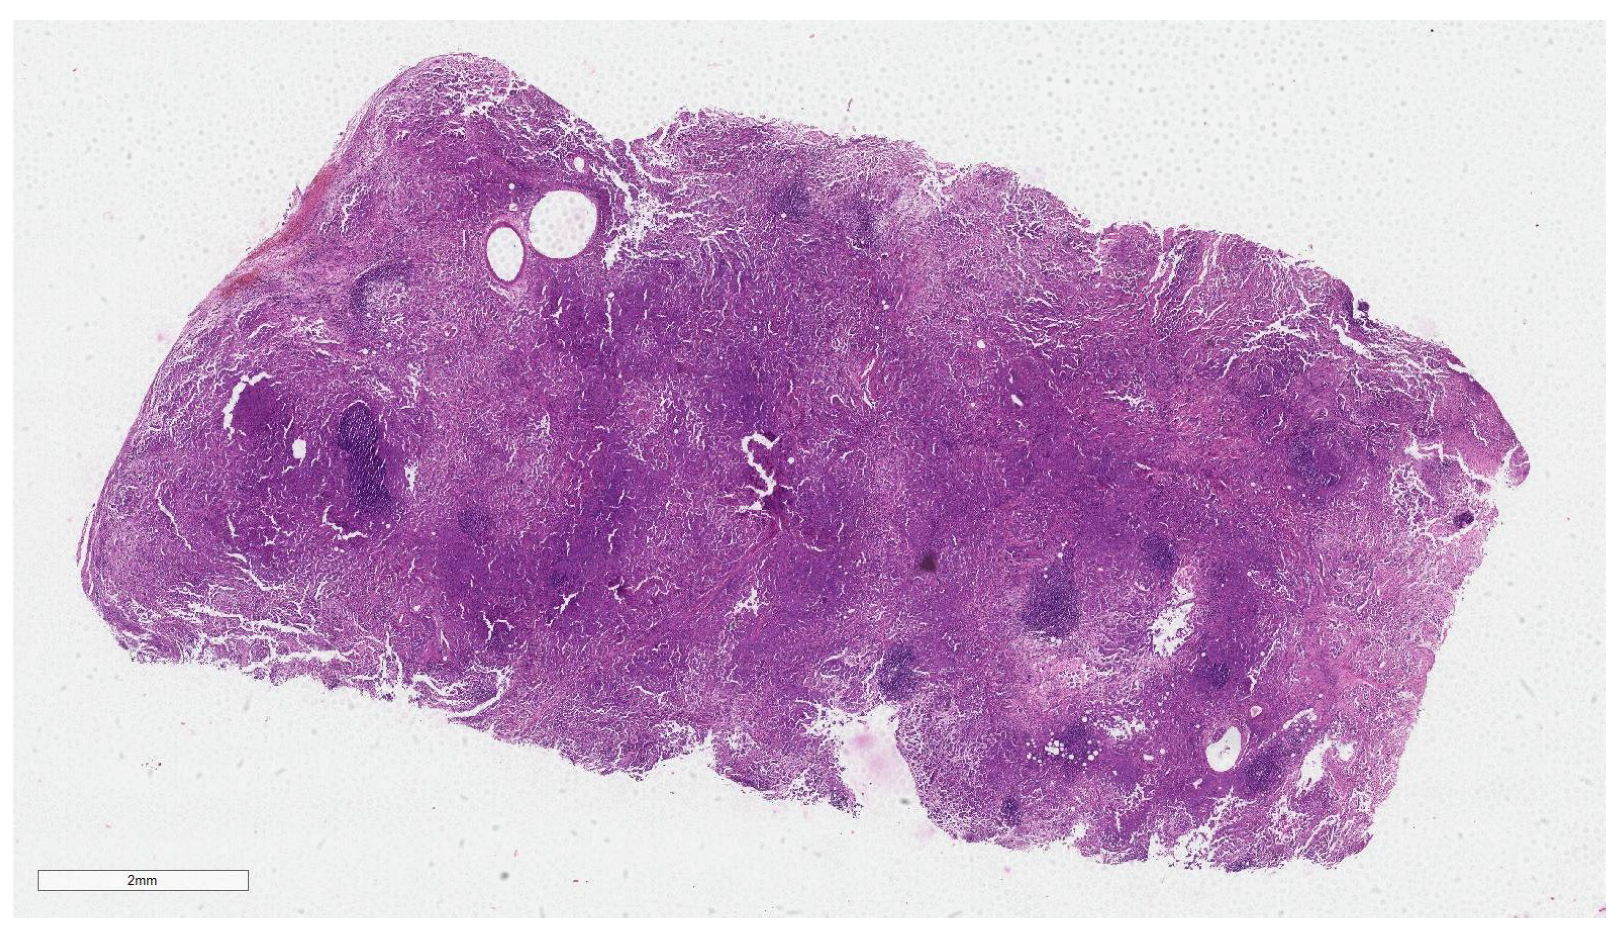

2.3. Dataset